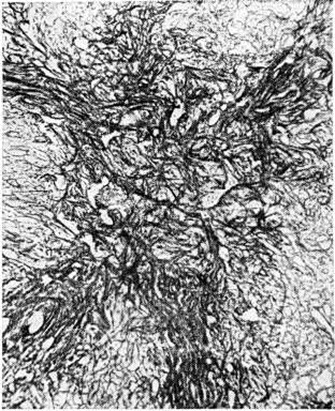

Микропрепарат ткани селезёнки при хроническом миелолейкозе после длительного лечения миелосаном: массивный фиброз пульпы и разрастание аргирофильных и коллагеновых волокон (в центре). Окраска по методу Тибор-Паппа; × 560

Указывается также на возрастание случаев фиброза в костном мозге, печени, селезёнке, особенно при хронический миелолейкозе (рисунок 14). Часть исследователей расценивают его как следствие заместительного разрастания соединительной ткани в ответ на исчезновение лейкозных инфильтратов под влиянием лечения. По мнению других, фиброзные изменения связаны с глубокой перестройкой структуры органов по ходу лейкозного процесса и удлинением сроков жизни больных. При хронический лимфолейкозе даже интенсивное лечение не сопровождается развитием миелофиброза, хотя могут иметь место перипортальный фиброз в печени и склероз пульпы селезёнки.

Описаны отдельные наблюдения распространённого нефрокальциноза (смотри полный свод знаний). Заметное снижение размеров лейкозных инфильтратов часто отмечается в селезёнке, лимфатических, узлах, печени (рисунок 11). В этих органах, как и в костном мозге, обнаруживаются различных размеров поля опустошения, геморрагического пропитывания ткани, группы лейкозных клеток с их распадом; при длительном течении возможно очаговое разрастание аргирофильных и коллагеновых волокон, частичное восстановление лимфатических, ткани в лимфоидных органах. При хронический длительно леченном миелолейкозе имеется резкий фиброз пульпы селезёнки с перестройкой её структуры (рисунок 12), участки липоматоза в лимфатических, узлах. Под влиянием лечения в связи с уменьшением объёма разрастаний все чаще при острых Лейкозы (даже при условии значительной продолжительности жизни больного) лимфатических, узлы, селезенка и печень сохраняют нормальные размеры и вес или бывают увеличены незначительно. При хронический Лейкоз, хотя размеры органов увеличены, однако не столь сильно, как до использования цитостатических средств.